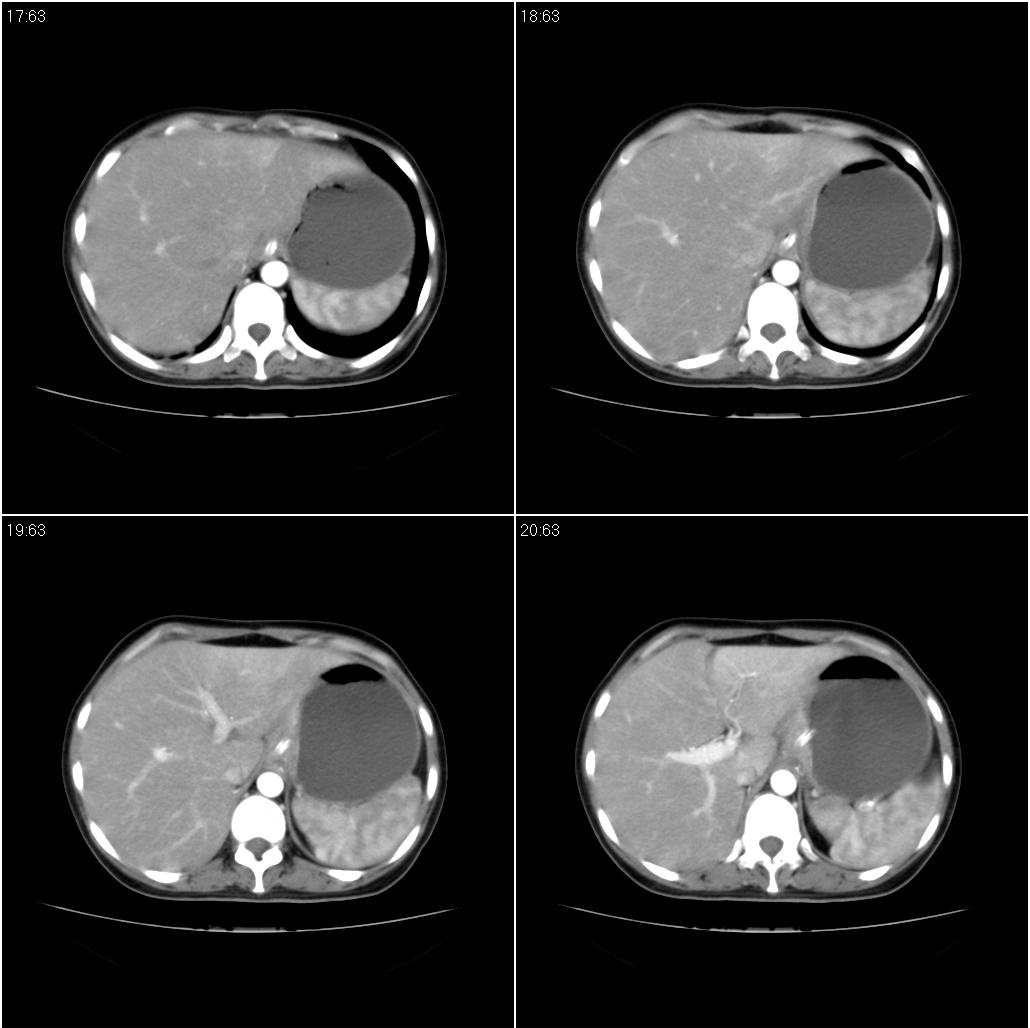

标题: CT21386:女性,33岁。4个月前因妊娠发现盆腔肿物。 [打印本页]

女性,33岁。4个月前因妊娠发现盆腔肿物。ca-125: 1100

胃癌,幽门梗阻

胃癌,幽门梗阻.

胃幽门部癌伴小弯侧和腹腔淋巴结转移,胃内有胃管。

胃窦贲门胃小弯好像都厚啊 ,胃窦处比较明显,而且胃腔扩张明显,考虑胃癌伴梗阻。